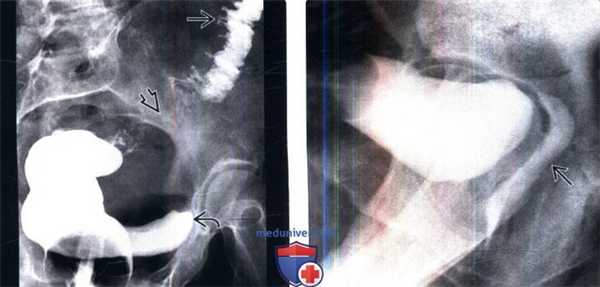

(Слева) Ирригография: у пациента с ободочно-пузырным свищом в анамнезе, возникшим вследствие дивертикулита, определяются несколько дивертикулов ободочной кишки, спазм сигмовидной кишки и заполнение мочевого пузыря контрастом, что указывает на наличие ободочно-пузырного свища.

(Справа) Цистография, выполненная через эпицистостому, боковая проекция: у пациентки с пузырно-влагалищным свищом в анамнезе, возникшим после гистерэктомии, определяется заполнение задних отделов влагалища контрастом.